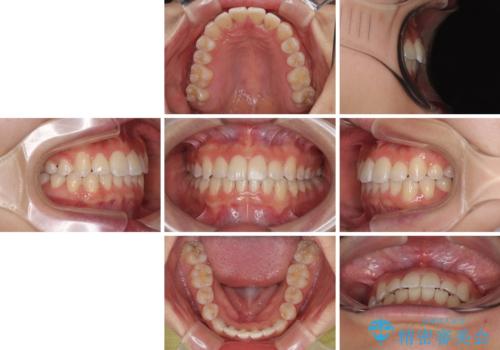

前歯のクロスバイト 裏側に隠れた歯をワイヤー装置で短期間治療

- 治療期間

- 1年2ヶ月

装置の外見を気にしていましたが、短期間で治療を終えることができるだろうと伝えると、安価であるメタルブラケットを選択されました。

想定通り、1年強で綺麗に仕上げることができました。